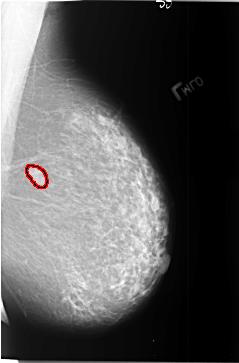

B_3405_1.LEFT_MLO

FILE: B_3405_1.LEFT_MLO.OVERLAY

TOTAL_ABNORMALITIES 1

ABNORMALITY 1

LESION_TYPE MASS SHAPE LOBULATED-OVAL MARGINS CIRCUMSCRIBED

ASSESSMENT 4

SUBTLETY 5

PATHOLOGY BENIGN

TOTAL_OUTLINES 1

BOUNDARY